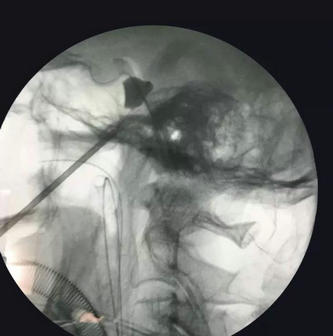

▲ 术中影像资料

“微球囊压迫技术—经皮穿刺微球囊压迫术治疗三叉神经痛,其优势明显:创伤小(仅在穿刺部位有一个针孔大小伤口),手术时间短(10到20分钟左右),疗效确切,复发率低,住院时间短、费用低,特别适合中老年、青少年及不接受开颅手术者,目前该微创治疗方式被绝大多数人群所接受。”寿记新教授介绍说。